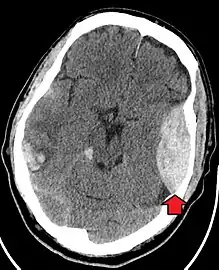

| Epidural hematoma as seen on a CT scan with overlying skull fracture. Note the biconvex shaped collection of blood. There is also bruising with bleeding on the opposite side of the brain. | |

Epidural hematomas usually appear convex in shape because their expansion stops at the skull's sutures, where the dura mater is tightly attached to the skull. Thus, they expand inward toward the brain rather than along the inside of the skull, as occurs in subdural hematomas. Most people also have a skull fracture.[3]

Non-contrast CT scan of a traumatic acute hematoma in the right fronto-temporal area.